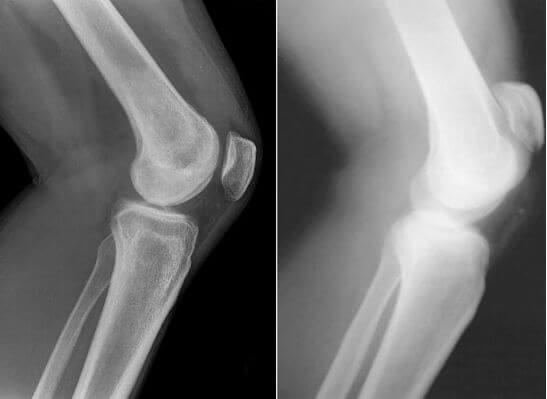

And here are pictures of joints before and after being treated with Maxiflex .

Restoration of the elbow joint. Woman, 31. Maxiflex treatment duration - 2 months. The joint has fully recovered.

The photos clearly show that Maxiflex doesn’t just alleviate the pain,but also starts the processes of regeneration of the synovial fluid - the function chondroprotectors are meant to perform. As a result, the cartilage layer becomes wider and more elastic - the joint improves, pain and stiffness disappear.